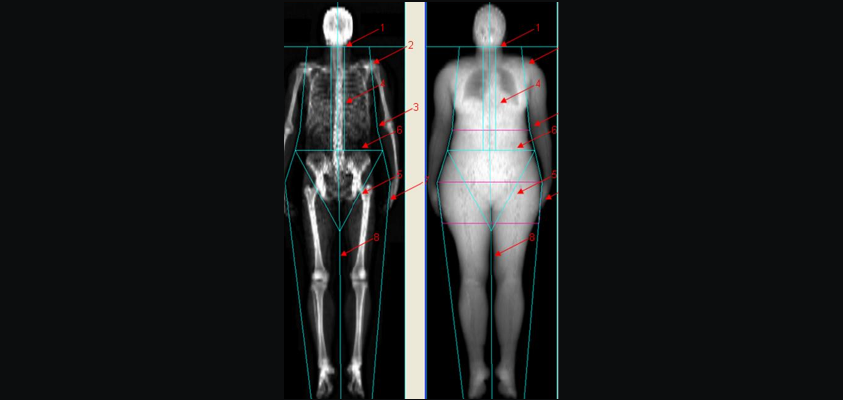

DEXA / BMD Test

(Bone Mineral Density Scan)

A DEXA scan, also known as a Bone Mineral Density (BMD) test, is a simple, quick, and non-invasive scan that measures the strength and density of your bones. It helps detect osteoporosis, a condition where bones become weak and fragile, increasing the risk of fractures.

The test uses low-dose X-rays to compare your bone density to that of a healthy young adult or someone of your age and gender, providing valuable insights into your bone health.